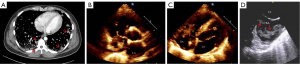

During a week of antifungal and antibacterial treatment, the patient’s symptoms did not improve significantly. Multiple infectious lesions in the lung and liver were thought to be caused by hematogenous disseminated infections that originated from macrovegetations in the heart. In the absence of an effective means to control the infection, after consultation and evaluation of cardiac surgeons, it was considered that the vegetation in the heart could be removed surgically to improve the infection and bleeding in the lungs. After thorough preparation, the surgery was performed on September 27, 2019. During the operation, a tumor was found in the right atrium, about 60 mm ×50 mm in size, which had invaded the atrial tissue. The mass was completely removed by the surgeon (Figure 2A). After surgery, endotracheal intubation and assisted ventilation were implemented, antifungal drugs were discontinued, and anti-infective therapy continued with vancomycin and meropenem. The patient’s vital signs were stable and SPO2 was 100%, but multiple bedside chest radiographs showed no significant changes in the bilateral lungs.

On the seventh postoperative day, the endotracheal tube was removed, and assisted ventilation continued. Fourteen days after surgery, the pathological results confirmed that the patient had a malignant vascular tumor (angiosarcoma; Figure 2B-2D). The doctor explained the condition to the patient and his family, and it was indicated that the patient’s intrapulmonary and intrahepatic lesions might be tumors and that the prognosis was poor. The patient had difficulty breathing and refused endotracheal intubation soon after, and the family also decided to halt treatment when he was in critical condition. The patient’s dyspnea worsened the next day, SPO2 was 70% under pure oxygen conditions, and the SPO2 continued to drop to 30% after endotracheal intubation. The patient became comatose and died.

Two months later, the girl returned to our hospital. She had developed intermittent left leg pain and a cough for about 1 month, accompanied by hemoptysis for 5 days. Routine TTE showed a solid mass in the right atrium (27 mm × 22 mm) that had high mobility and was lobulated, and it was considered a malignant lesion (Figure 3C). The CT review suggested pleural metastasis in the right lower lung, so an ultrasound-guided biopsy with a 20-G biopsy gun (BARD® MAGNUM®) was performed on the pleura. However, the pathological finding was also infectious disease. To explore the nature of the atrial mass, further contrast echocardiography (CE) was performed, revealing a very rich blood supply within the mass. The perfusion intensity and time were similar to those of the myocardium, and there was no necrosis. The mass was diagnosed as a malignant tumor (Figure 3D). Then, positron emission tomography (PET)-CT was used to determine whether there were metastases throughout the body, and clear positive results were obtained. The right atrial mass was a primary cardiac malignancy (Figure 3E), and there was a metastasis between the muscles of the right middle thigh (Figure 3F). Ultrasound-guided biopsy with a 20-G biopsy gun (BARD® MAGNUM®) for the mass in the right thigh was performed, and the pathological result was Ewing sarcoma (Figure 4A-4D). A vindesine, ifosfamide, doxorubicin, and etoposide (VIDE) chemotherapy regimen was then used for the patient.